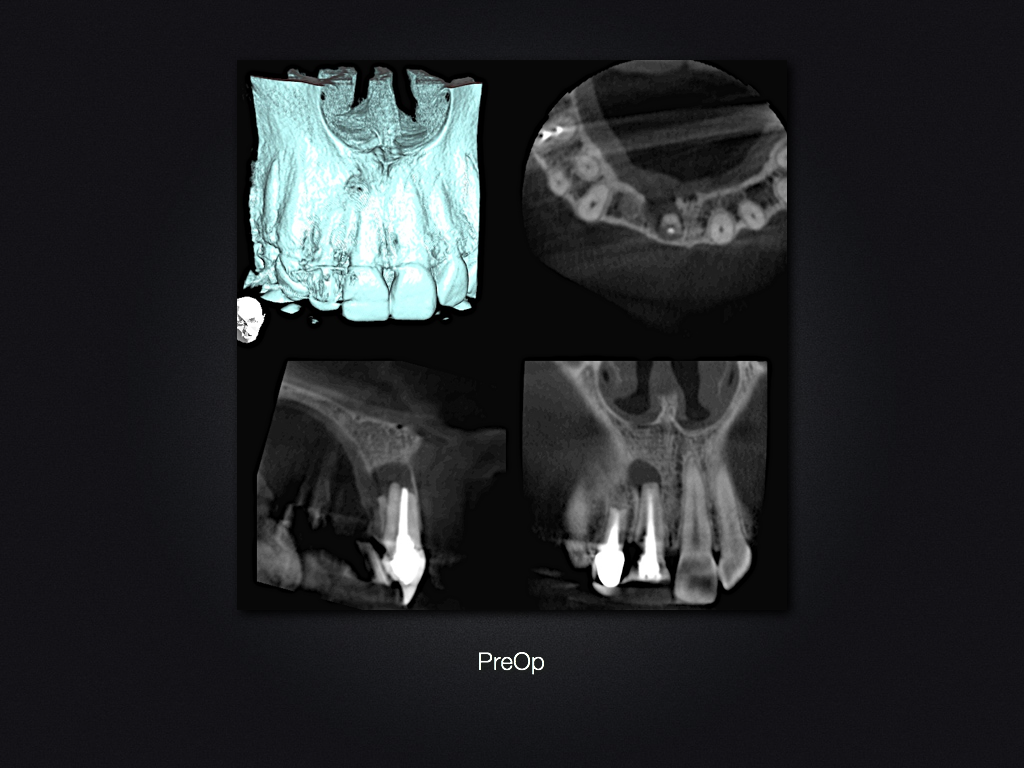

11D.011

Und es heilt doch!